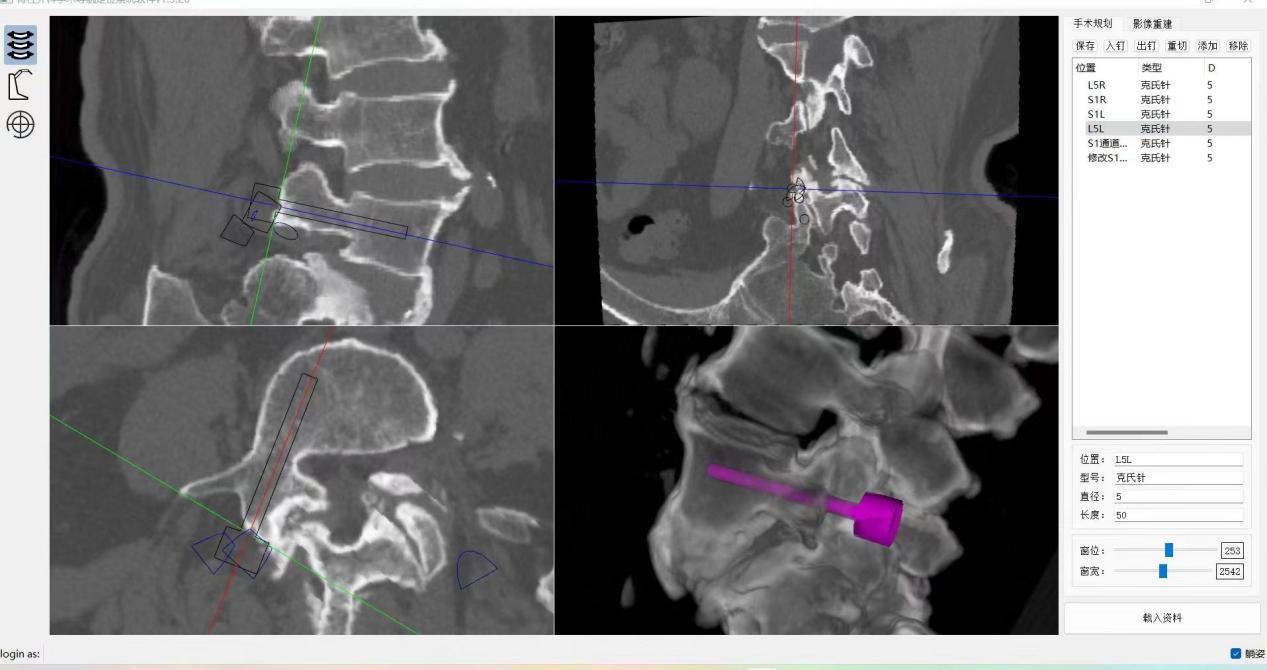

,均建议采取传统外科开放手术治疗,患者因担心手术风险,迟迟不愿手术。经多方打听,患者慕名找到李全义主任医师。入院后李全义主任医师仔细研究患者的疾病特点,经过充分的沟通,决定采用目前骨科先进的微创、精准技术—机器人辅助微创手术。李全义主任医师团队顺利为患者实施ORTHBOT脊柱机器人辅助镜下腰5椎体滑脱复位椎管减压椎间融合内固定术,以机器人辅助微创手术解决了患者的痛苦,减少手术创伤及并发症,缩短手术时间。手术利用术前患者的影像学资料,模拟建立穿刺路径及各项参数,极大地优化手术方案使其更加精准、安全、有效,显著降低了制钉过程中神经根损伤的风险。

ORTHBOT脊柱机器人术前设计及术中穿刺